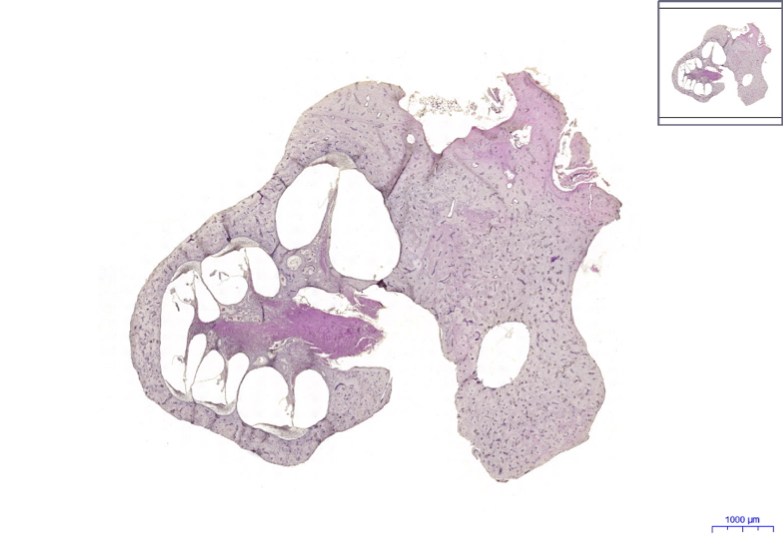

Organum vestibulocochleare – HE, 0.8x

Organum vestibulocochleare: